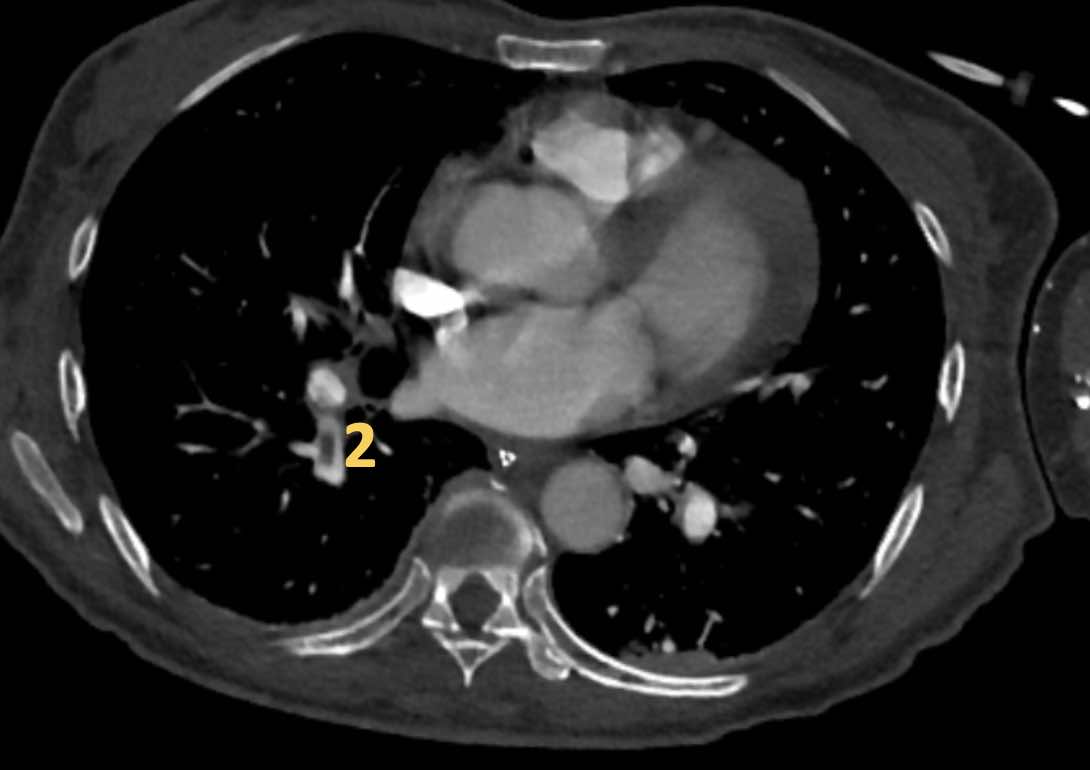

Đây là các hình ảnh của bệnh nhân nữ 59 tuổi tại khoa cấp cứu,

minh họa rõ ràng các huyết khối ở các mức độ khác nhau.

Cuộn qua các hình ảnh.

- Huyết khối trong động mạch thùy đến thùy trên phổi phải.

- Huyết khối tại lỗ vào của động mạch phân thùy đáy sau của thùy dưới phổi phải.

- Huyết khối dưới phân thùy ở phân thùy đáy trước của thùy dưới phổi phải, vài nhánh phía sau động mạch phân thùy.

- Huyết khối tại chỗ phân đôi phân thùy của thùy trên phổi trái.

- Huyết khối tiếp tục lan về phía ngoại vi trong động mạch dưới phân thùy.